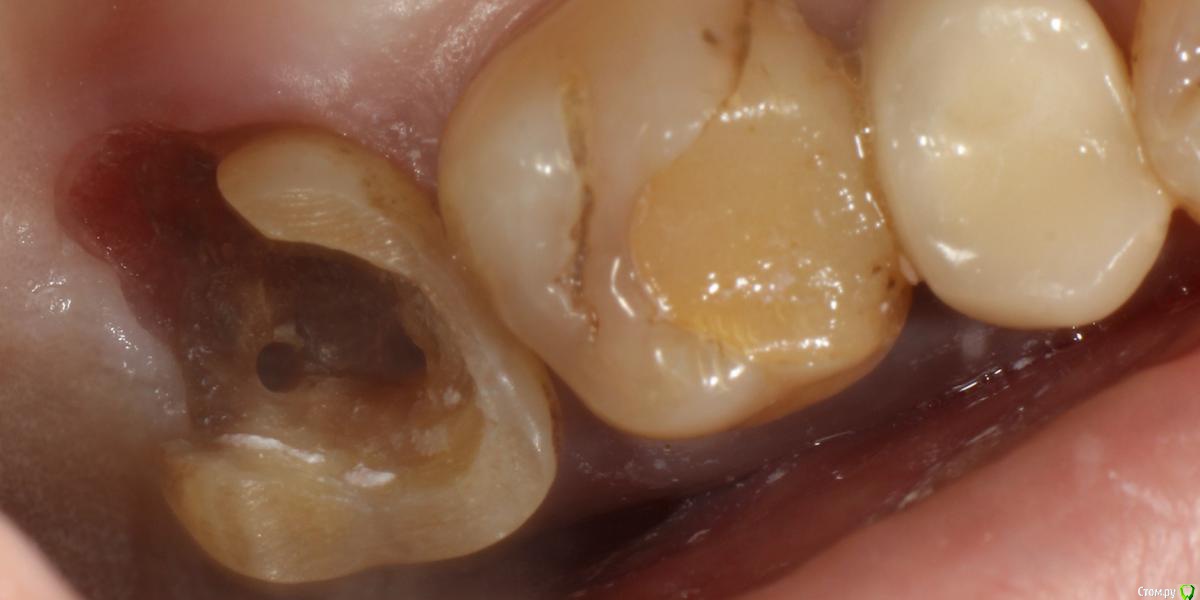

В начале своей карьеры...давным давно...где-то год назад удалял верхнюю восьмерку. Тогда я не знал, что при наличии пломб-залипух на соседних зубах, нужно предупреждать, что они могут вылететь. Что и произошло с 1.7 Пациент оказался адекватным, все понял, сказал через неделю придет, поставим пломбу и happy end. Прошел год - пришел пациент. На мое предложение удалять, так как от зуба немного осталось, а неделя неравна году, была сказана фраза: "на соседнем зубе тоже пломба-залипуха, так я вообще без зубов останусь". Ну надо воевать, подумал я. Изначального фото ситуации нет, но там пришлось убирать достаточное количество десны. (За фото прошу не пинать, бить только руками)

post-52119-0-37089500-1559803596_thumb.jpg

Стандартная обработка машинными, с кофером, ГХ, блекджеком и...

post-52119-0-31081100-1559803692_thumb.jpg

Пломба(СО ШТИФТОМ), сильно полировкой заморачиться не стал, так как в это же посещение обработка под МК